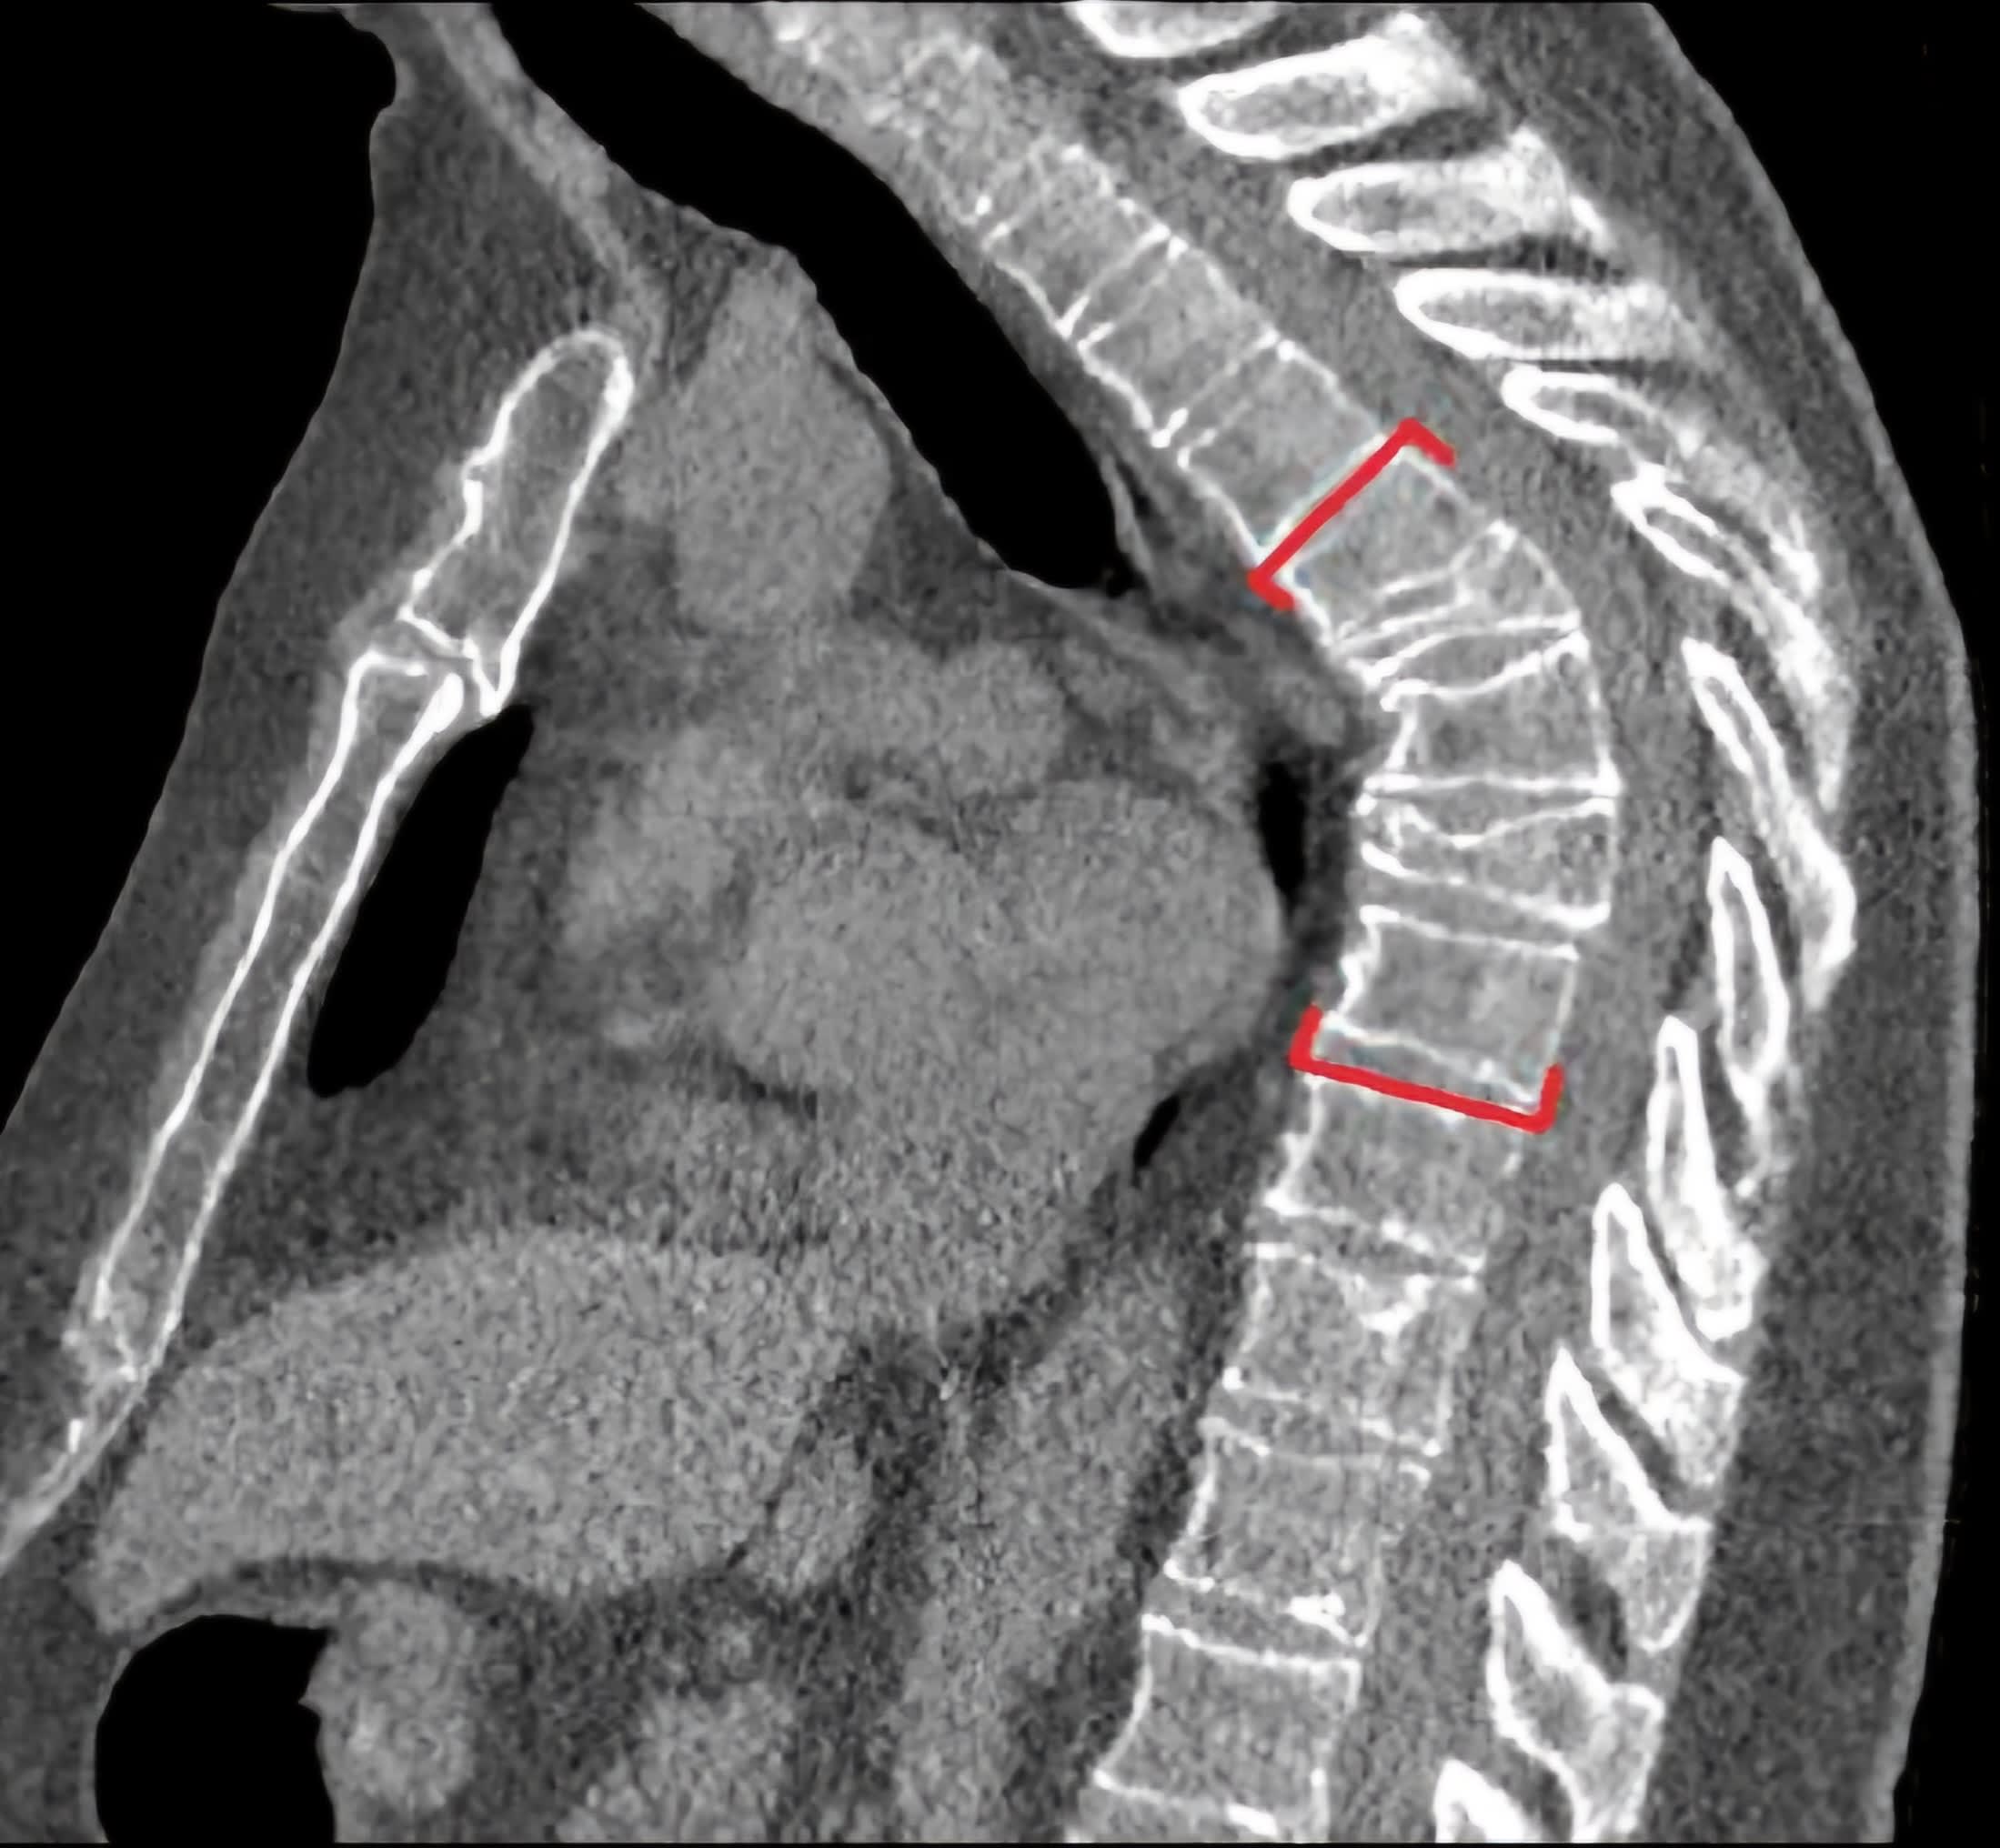

@honeybeehives3 I’m certainly still dealing with pain. I knew it would be lifelong so I’m thinking my attitude was good. Here’s a lateral view of my spine. I extracted it from an annual CT of my chest. The red brackets show the top and bottom of the 5 affected.

19 years ago I was in a MVA. I was in the hospital and my insurance was covering inpatient OT/PT. At this point the big things I was dealing with 6 pins in one hand holding my fingers together and an amputation of part of a foot. Oh, and the pain. OMG, the pain. During a therapy session I commented to the therapist that when I moved my arm like this (demonstrated the motion) it feels like dirty bearings. IYKYK. She placed her hand on my right shoulder blade and had me demonstrate again. She felt it. PT stopped and I was sent for more xrays. They assumed it was the shoulder blade. Shoulder blade was a-ok but there was something at the edge of said xray. Next was CT of the entire spine. BINGO!!! 7 broken ribs, 5 crushed vertebrae and a sternum fracture. This was day 8 post accident. I was fitted for a clamshell brace and discharged in 2 days. Without any plan for moving forward. In hindsight I’m sure it just scared the crap out of them for malpractice liability but be for real. 6 months later I was back at work. I’ve been on heavy narcotics (during the opioid crisis, wheeeee!) since. Mid August I was approved for disability through my insurance company. The last ~18 months were grueling. Insurance would not approve an increased pain medication dose and I couldn’t take it anymore.